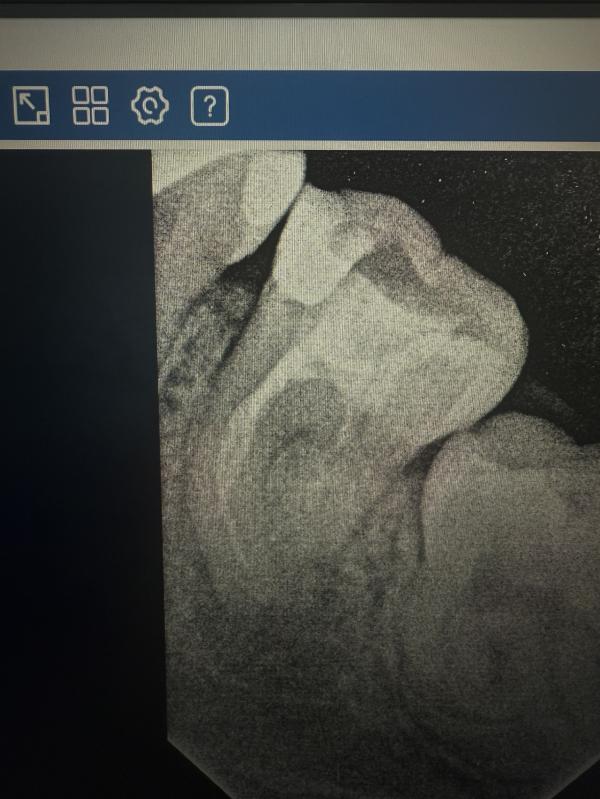

Зуб лечен очень давно, я еще училась только на первом курсе. Как видно на снимке лечен один канал вообще почти не запломбирован. Из за этого образовалась киста.

А что самое смешное, что он меня совсем не беспокоил, пока я не решила на него надеть коронку и ортопед отправил меня на перелечивание под микроскопом. Но и микроскоп не помог. После этих попыток, он начал побаливать на давление (горе от ума, как говорится🤣)И вот спустя три года образовалась киста и зуб ушел на удаление. Поэтому микроскоп не всегда панацея. Все слишком индивидуально. У каждого.